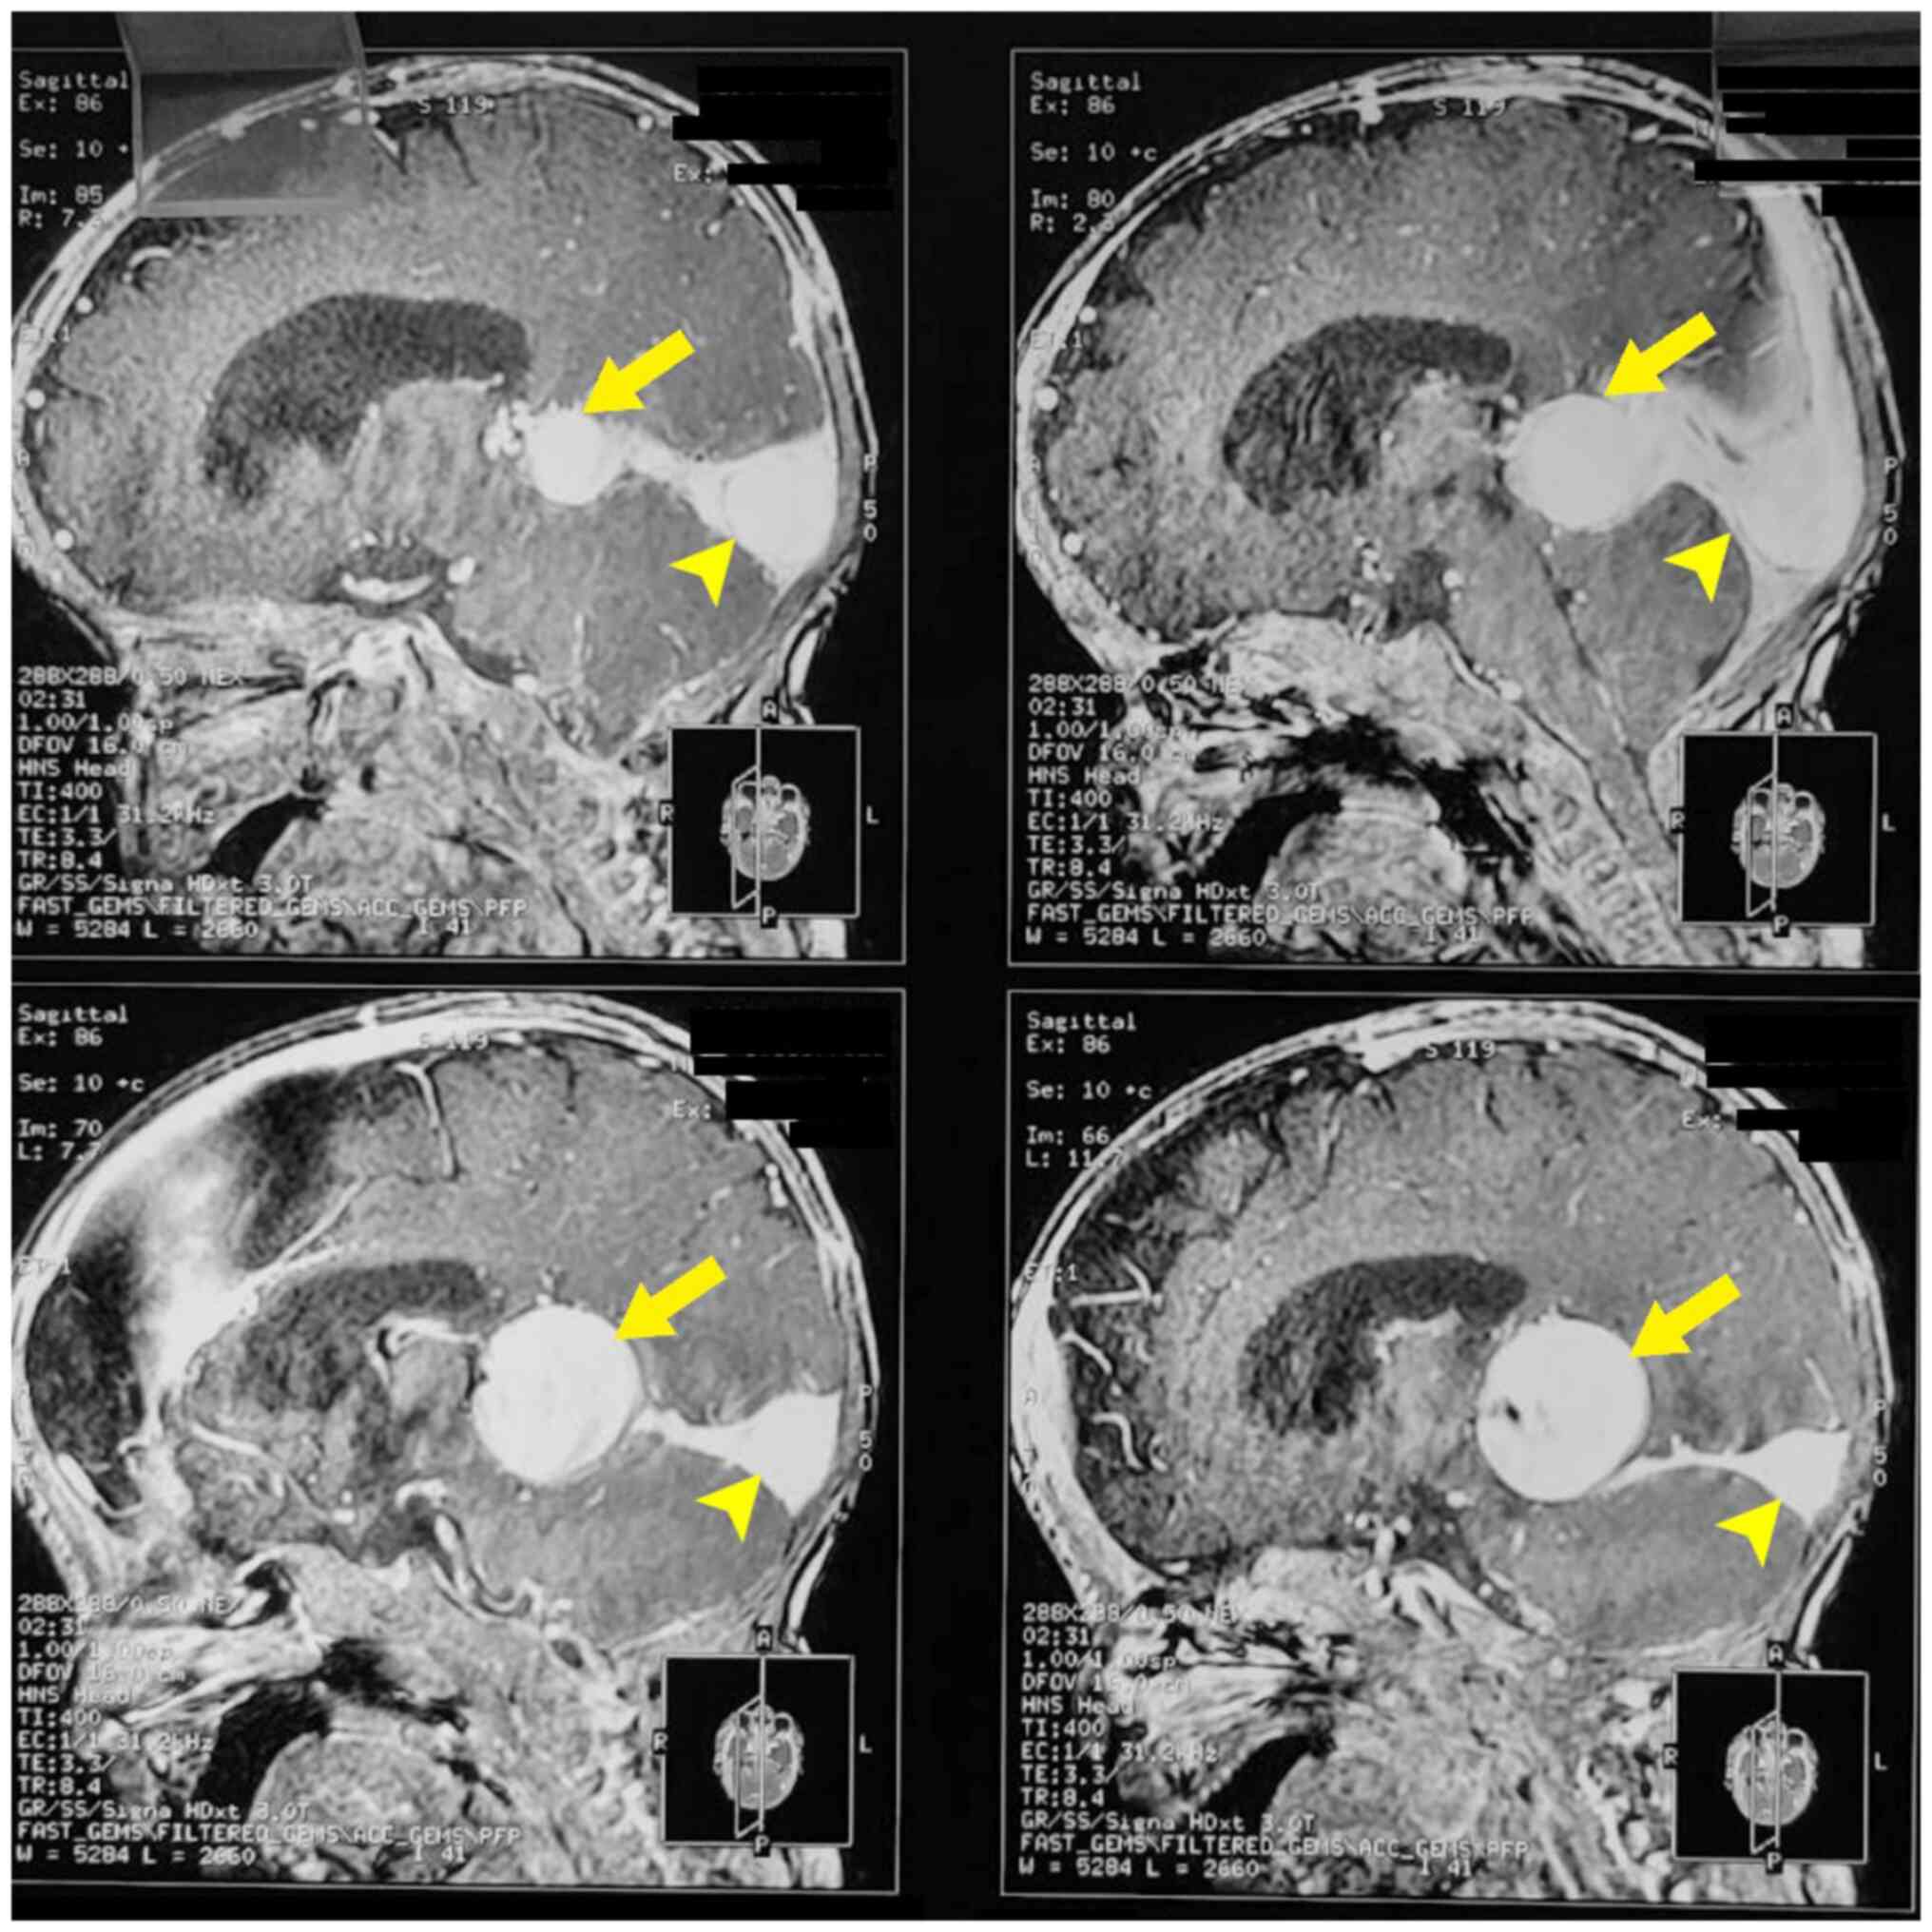

Intracranial vein of Galen malformation and its management: A case report

Vein of Galen malformation (VOGM) is a rare congenital arteriovenous malformation affecting the pediatric population, characterized by a fistula between the diencephalon and a dilated vein of Galen. The present study reports the case of a 6‑month‑old male infant referred for developmental delays and abnormal head circumference. A clinical examination revealed macrocephaly, dilated scalp veins and neurological abnormalities. Neuroimaging confirmed a large VOGM with associated hydrocephalus. A multidisciplinary team devised a treatment plan involving endovascular embolization and ventriculoperitoneal shunt placement. The post‑operative recovery exhibited an improvement in neurodevelopmental milestones and a reduced head circumference. Generally, the management of VOGM requires a comprehensive approach, including early diagnosis, precise imaging and timely intervention. The case described herein highlights the importance of interventional radiology in planning a management plan and the novel kissing microcatheter endovascular embolization technique.

Figure 2

Figure 3